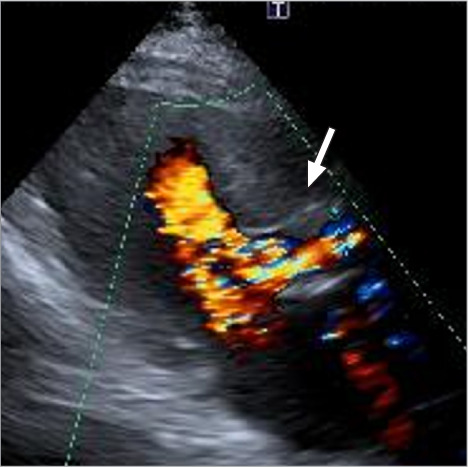

本报告重点介绍了第二代雅培Trifecta Glide技术生物人工心脏瓣膜早期结构性瓣膜恶化并尖端撕裂的病例。一名70岁的男性在30个月前因严重的二尖瓣主动脉瓣狭窄接受了triecta Glide技术瓣膜置换术。经胸超声心动图显示,患者因主动脉瓣严重反流导致急性心力衰竭并呼吸困难,同时出现Trifecta Glide Technology瓣膜尖端撕裂。患者通过紧急重复主动脉瓣置换术成功治疗。

This report highlights a case of early structural valve deterioration with a cusp tear in a second-generation Abbott Trifecta Glide Technology bioprosthetic heart valve. A 70-year-old man had undergone aortic valve replacement with a Trifecta Glide Technology valve 30 months earlier for severe bicuspid aortic valve stenosis. He suddenly developed acute heart failure with dyspnea resulting from severe aortic valve regurgitation, with a cusp tear in the Trifecta Glide Technology valve, as demonstrated by transthoracic echocardiography. The patient was successfully treated with urgent repeat aortic valve replacement.